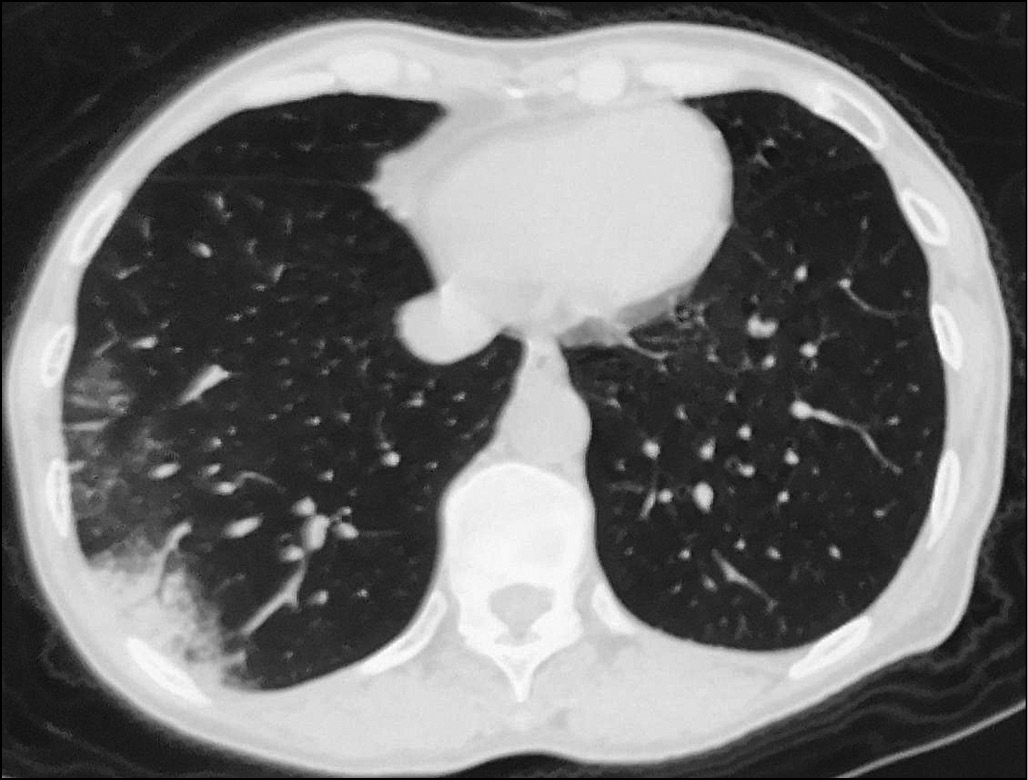

Компьютерная томография. Всего за время исследования получено 115 результатов КТ лёгких. По первым КТ-изображениям, выполненным до лечения, у 45,3% пациентов выявлен симптом «матового стекла», у 65,6% — бронхит, у 21,9% — фиброз, у 14,1% — кальциноз, у 12,5% — узловые образования. У 2 пациентов обнаружено утолщение плевры, у 3 — каверна лёгкого, у 2 — застарелый туберкулёз лёгких. Согласно результатам, между двумя возрастными группами не найдено статистически значимого различия по большей части поражений (p > 0,05); табл. 1, рис. 1–3.

Рис. 1. Симптом «матового стекла» в нижней доле правого лёгкого.